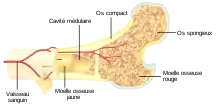

Les os sont composés d'une substance compacte se trouvant à l’extérieur de l'os, et d'une substance spongieuse se trouvant à l’intérieur de l'os. Cette substance spongieuse ressemble à une éponge rigide et réserve des cavités plus ou moins grandes entre la substance osseuse (les trabécules)[1]. Ces cavités sont remplies par une matière appelée moelle osseuse[2].

Les cavités osseuses sont tapissées de cellules qui construisent les os (les ostéoblastes), et de cellules, moins nombreuses, qui détruisent les os (les ostéoclastes). Cette activité de construction et destruction osseuse est permanente à tous les stades de la vie et est nécessaire à la solidité des os[3]. Les cavités sont remplies par un gel fibreux, la matrice extracellulaire[4], qui soutient les différents composants de la moelle osseuse. Cette matrice contient un réseau de petites artères et veines (les capillaires), des cellules de soutien (les fibroblastes), des cellules nerveuses, des cellules de graisses (les adipocytes), des cellules sanguines à différents stades de maturation (les cellules hématopoïétiques), et de la réticuline, une protéine de soutien similaire au collagène[5]. De plus, des cellules stromales sont aussi présentes[2] ; ces cellules semblent jouer un rôle important dans la formation des cellules sanguines[6].

Il y a deux types de moelle osseuse[2] :

- La moelle osseuse rouge, comportant peu d'adipocytes et proportionnellement beaucoup de cellules hématopoïétiques, et ;

- La moelle osseuse jaune, comportant beaucoup d'adipocytes et peu de cellules hématopoïétiques.

Le sang arrive à la moelle osseuse par un vaisseau sanguin qui entre dans l'os au milieu de celui-ci. Ce vaisseau se ramifie de plus en plus et après avoir drainé l'os arrive dans la moelle osseuse par des petits vaisseaux, les capillaires. La paroi de ceux-ci (l'endothélium) est constituée de cellules plates entre lesquelles les cellules sanguines arrivées à maturation passent dans le sang[5].